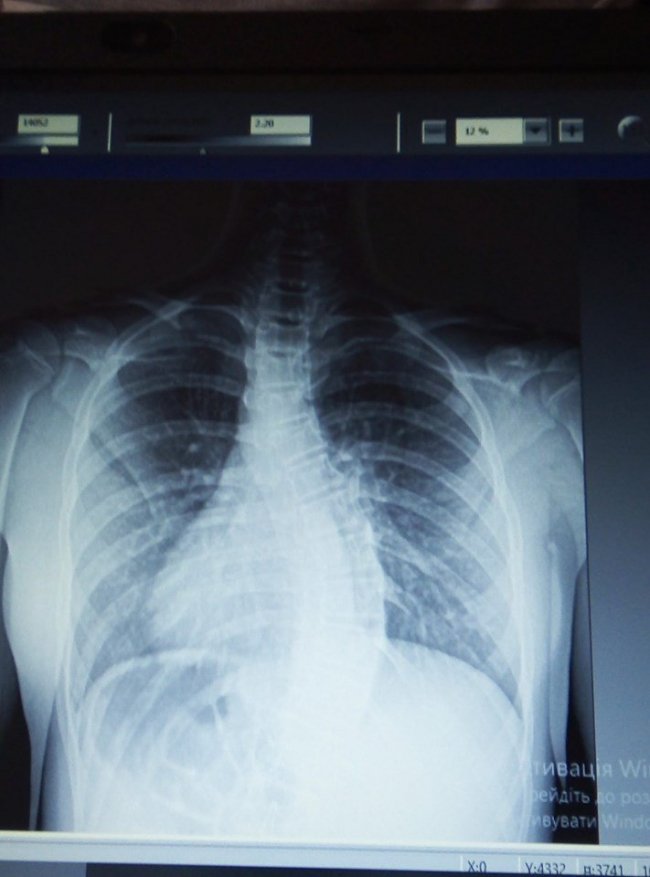

У 13-річної Анастасії, яка родом з Володимира-Волинського – сколіоз третього ступня (ідіопатичний грудо-поперековий).

Дівчинка має інвалідність, а хвороба й далі прогресує, - пише Володимир медіа.

Допомогти може складна операція з встановленням складної конструкції у спину, яка дозволить тримати хребці у правильному положенні. Вартість встановлення – 180 тисяч гривень.